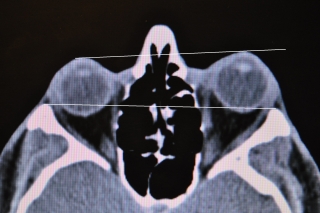

Fig.1: Exoftalmo unilateral de 4mm por aumento del volumen del tejido orbitario (grasa y músculo recto interno). Hay dos formas para corregir el exoftalmo:

1. Lipectomía (quitar grasa orbitaria), 2. Laminectomía (abrir paredes de la órbita)